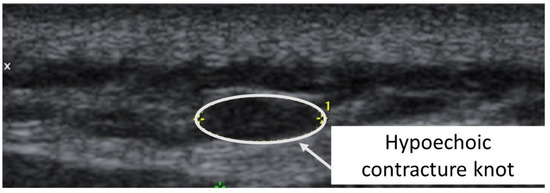

The second case was a 5′6”, 130 lbs., 26-year-old female subject (previously evaluated by both primary care physician and doctor of physical therapy to rule out other causes of symptoms other than TrPs) with left temporal headaches previously successfully treated by TrP-DN of the left upper trapezius. A taut band with palpable nodule within the left upper trapezius muscle was identified. As had been the case with previous headaches, the subject reported, upon palpation, pain referral symptoms spreading up the neck, around the ear, and into the temple [32]. The nodule was subsequently imaged in long-axis with a General Electric Voluson i Ultrasound System with a 12L-SC 13 MHz linear probe. A large hypoechoic contracture knot (61 mm × 22 mm) was identified (Figure 5) with smaller hyperechoic “speckles” (Figure 6) within the hypoechoic contracture knot (approximately 1 mm × 1 mm).

Figure 5.

Ultrasound imaging assessment of the left upper trapezius muscle showing a palpable contracture knot as a hypoechoic (hyperperfused) area.

Considering that the pathogenesis of TrPs consists of dysfunctional motor endplates and they are ischemic areas in nature, previous studies may have mislabeled contracture knots as TrPs [19]. In each case presented, a hypoechoic/hyperperfused area of approximately 1 cm × 1 cm was visualized in the vicinity of the palpable nodule, with small hyperechoic/nonpalpable speckles of approximately 1 mm × 1 mm within each. Consistent with the multiple loci hypothesis presented by Hong and Simons [25], we suggest that the relatively large hypoechoic structures visualized as the TrP area in both subjects examined represent hyperperfused contracture knots with smaller, not previously distinguished, ischemic and hyperechoic TrPs within each.